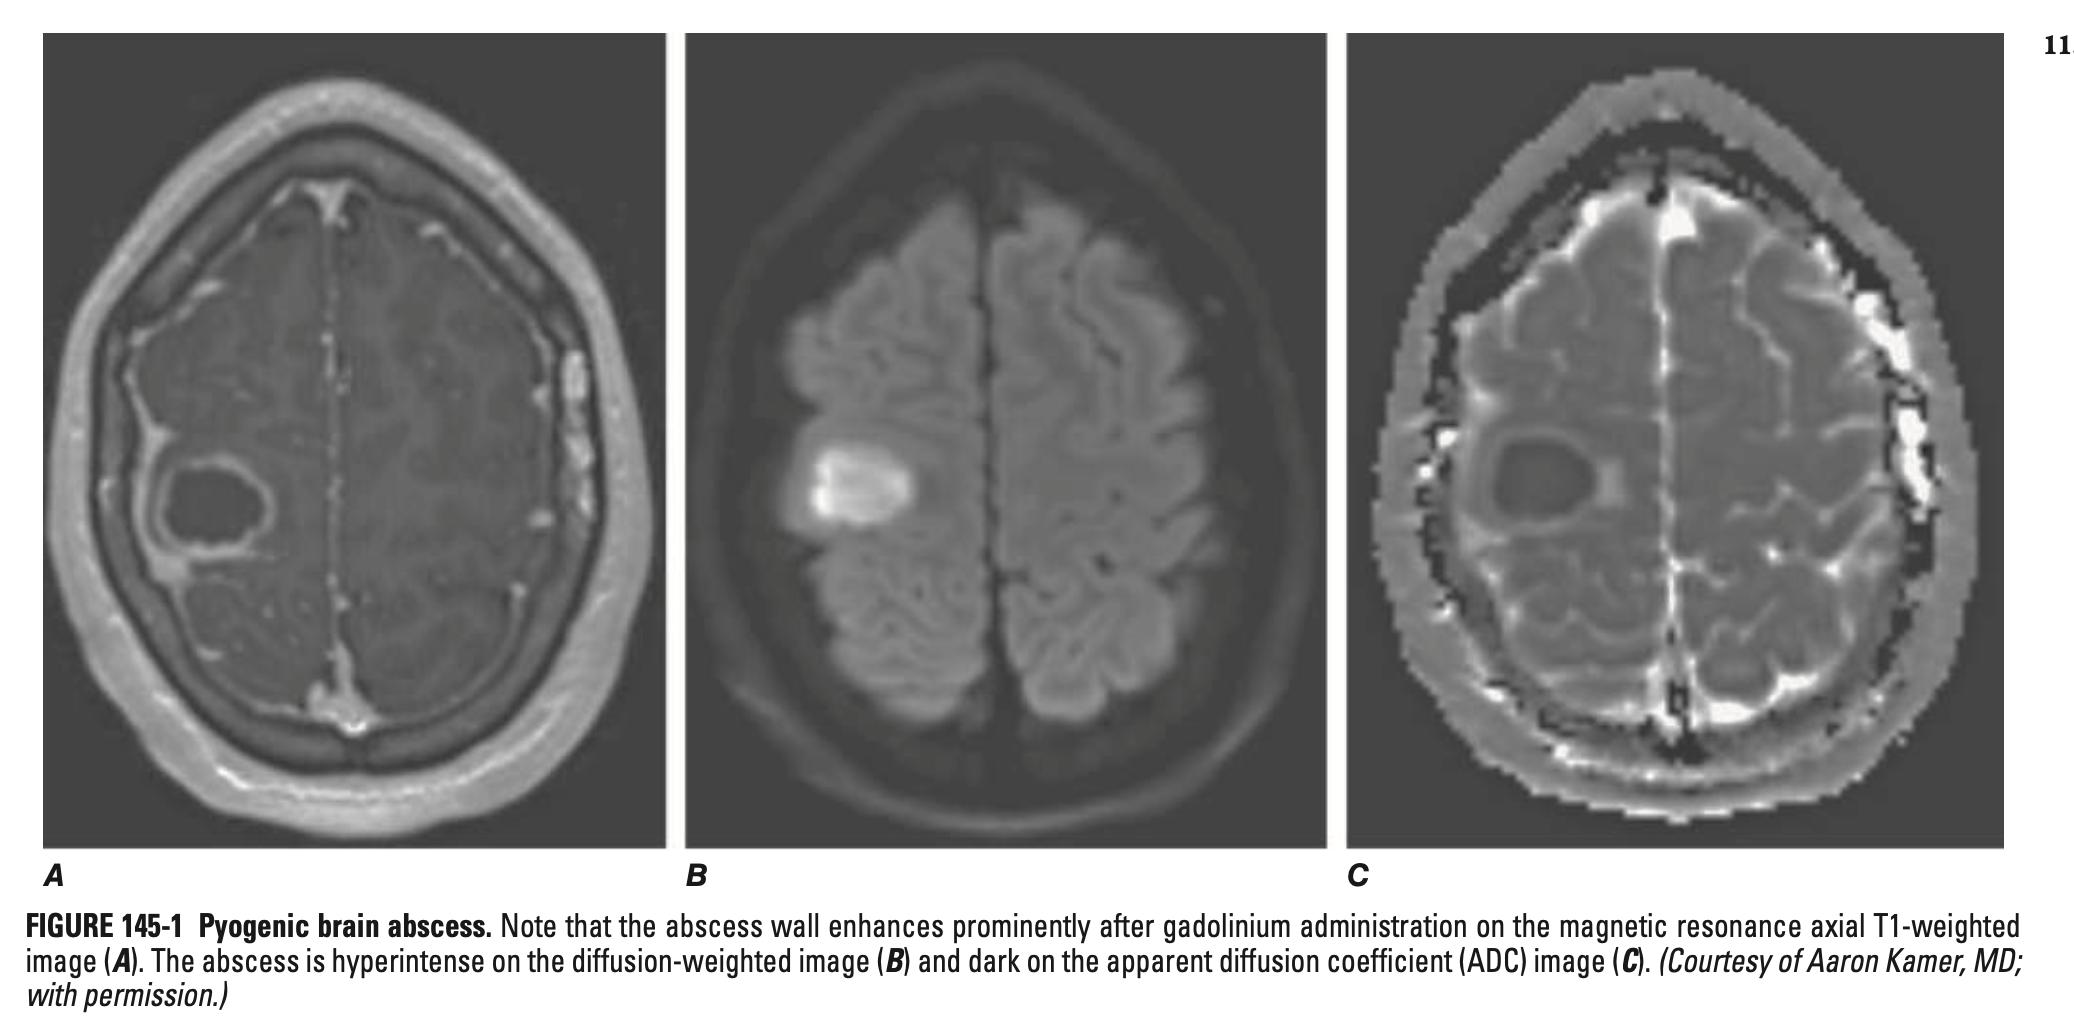

뇌농양 (Brain abscess)

• 정의: 뇌 실질에 발생한 국소적 화농성 감염, 혈관화된 피막 형성

• 진단 및 검사

• 영상검사: MRI (DOC), CT